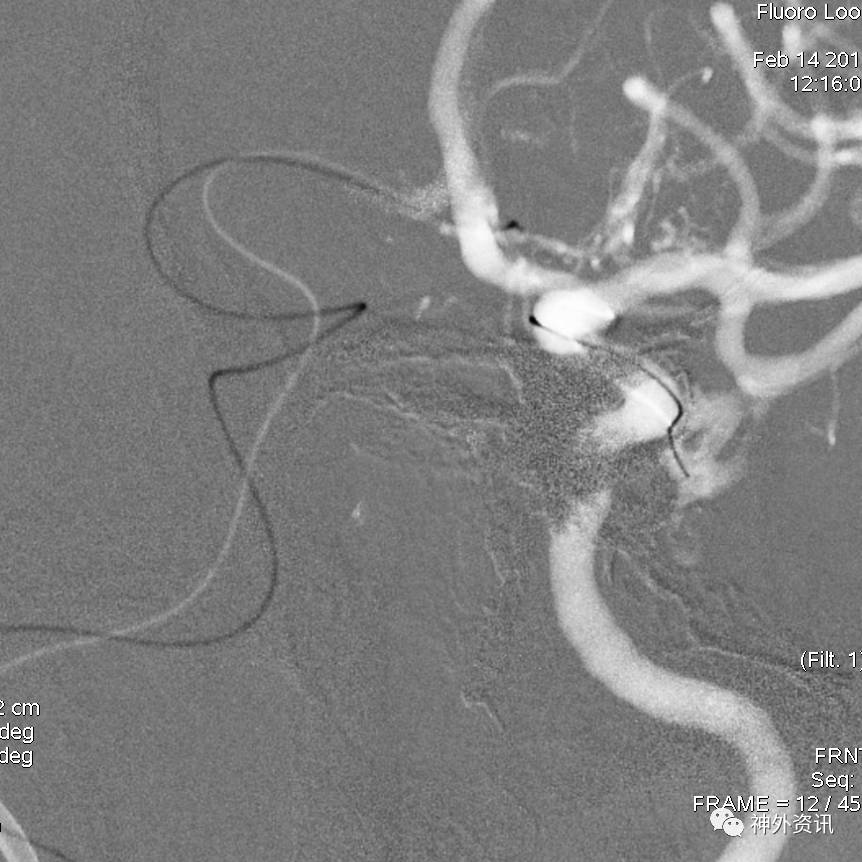

眼动脉动脉瘤,支架完全释放后,微导管成袢逆行到位

病例二

眼动脉动脉瘤,支架释放前,微导管成袢逆行到位